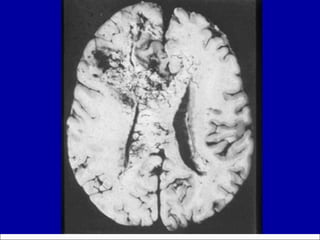

Glioblastoma:  post-mortem